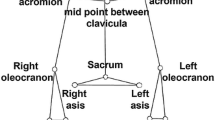

Subjects were seated with the affected (patients) or dominant (controls) arm fully suspended in a splint that was attached to a force sensor (AMTI-300, Advanced Mechanical Technology Inc., Wavertown, MA, USA). The two translational degrees of freedom perpendicular to the humerus were fixed, and the longitudinal translation and three rotational degrees of freedom were released (Fig. 1). The splint allowed for variation in point of force application (force sensor) alongside the humerus. In this way, external moment loading can be varied, without changing task force magnitude. Subjects were instructed to maintain the arm in a standardized position during the experiment: arm elevation of 60°, 30° of horizontal abduction with the humerus 45° internally rotated, as applied in previous studies with this setup [3, 4, 16, 23, 26, 27]. Arm position was visually controlled for by markings on the experimental setup. The arm was fully supported for gravity in this specific condition, so subjects were able to maintain the arm this way without any effort.

Setup for isometric tasks with a small or large moment arm of an external task force. In the current study, we applied abduction tasks. For these tasks, subjects had to move a cursor (red dot) to a target (blue dot) randomly representing each of seven, respectively, applied equidistant abduction directions, 15° apart, ranging from pressing arm straight up (0°, a) to pushing the arm sideward (90°, b). The point of force application, i.e., where the force sensor is attached to the splint, can be varied in order to realize large moments (a) or small moments tasks (b), while keeping the exerted task force constant (color figure online)

Subjects performed isometric abduction tasks perpendicular to the longitudinal axis of the humerus. By applying forces onto the force sensor, subjects could control a visually displayed cursor (red dot) that had to be moved to randomly appearing targets on a computer screen. Each target represented a force vector of constant magnitude in one of seven equidistant abduction directions (15° apart), away from the midline or sagittal plane of the body and in the scapular plane, ranging from 0° (push arm straight up) to 90° (push arm sideward; Fig. 1). Subjects held the cursor within each target area for 2 s. Force magnitude was determined individually during each session and set at 10 N below the maximum level at which subjects could perform the 2-s tasks, as recommended previously, with a minimum of 10 N to secure sufficient signal over noise ratio [25]. After practice rounds, two task trials were performed: one trial with the point of force application at about 10 cm distally from the GH joint, i.e., the ‘small moment arm’ condition, and one trial with the point of force application approximately 25 cm distally from the GH joint, i.e., the ‘large moment arm’ condition. Note that within each session, the force magnitude was constant for the two trials. In order to prevent fatigue and other carry over effects, there was a minimal 15-s rest period between the tasks and a period of 5 min between the two trials.